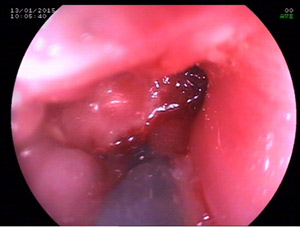

His gastroscopy was done and the scope could not be negotiated across tha anstomosis.The wire could not be passed under fluoroscopy for dilatation with another gastroenterologist .

I could pass a wire and dilate the esophago-jejunal anastomosis with placement of a covered metallic self expandeble stent for palliation of dysphagia with half of the covered stent in the j-shaped jejunum and half proximally.